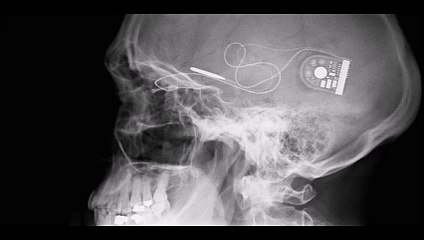

Notre mémoire fonctionne à 99 avec ce qui est déjà enregistré dans notre cerveau. Nous ne pouvons pas tout mémoriser de façon consciente. La mémoire est donc sélective.